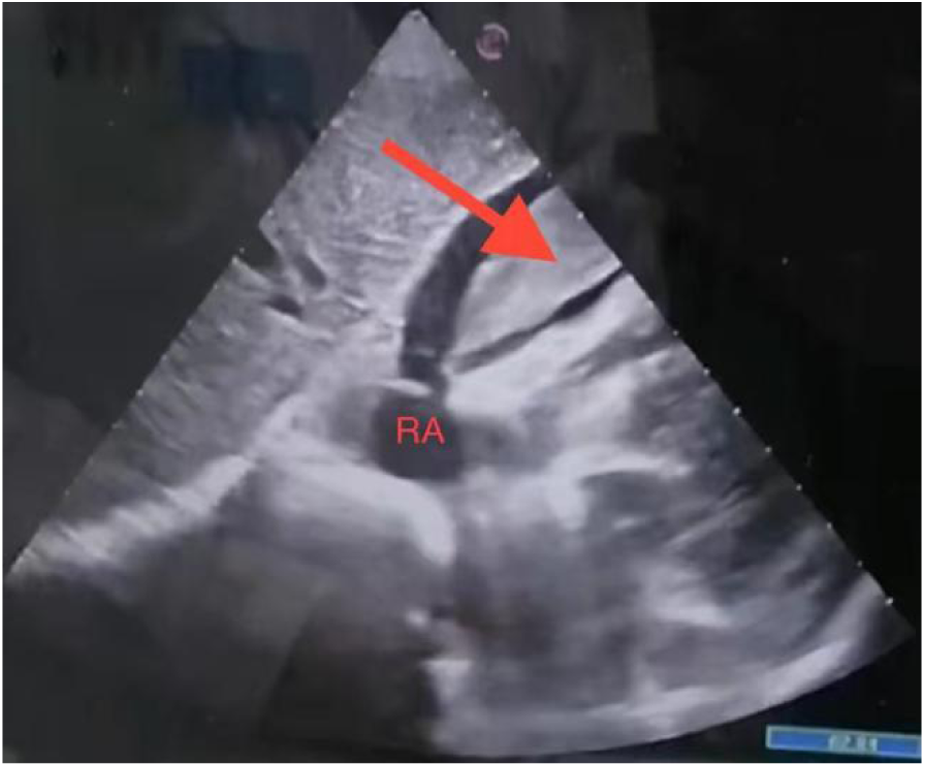

A 69-year-old woman was brought to the emergency department with complaints of chest pain and syncope. Eight hours prior, the patient had undergone acupuncture therapy at a local clinic to treat heart palpitations. The acupuncture was performed below the xiphoid process. Approximately ten minutes after the needles were inserted, the patient suddenly lost consciousness. Upon regaining consciousness, she reported severe chest pain, accompanied by dizziness, palpitations, sweating, nausea, and vomiting. She was then transferred to the nearest county hospital. Upon arrival at the county hospital, her vital signs were as follows: blood pressure 75/42 mmHg (1 mmHg = 0.133 kPa) and pulse rate 90 bpm. An echocardiogram, provided via video by her son, revealed a large mass within the pericardial cavity along with pericardial effusion (Figure 1). Despite intravenous dopamine infusion, the patient's symptoms of chest pain, dizziness, palpitations, sweating, and nausea persisted, and her blood pressure remained low at 85/66 mmHg. The patient denied any history of hypertension, diabetes, cardiovascular disease, and family history of Marfan syndrome. Additionally, there was no history of trauma or prior surgeries.

Figure 1

Subxiphoid four-chamber view: pericardial effusion and a mass were observed.